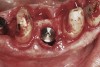

Apparently with time, stable implants placed with low initial torque develop bone characteristics around them that are similar to sites where implants were placed with a high initial torque (Figure 4 and Figure 5). Conversely, for implants placed with a high initial torque, the healing process, despite the high initial torque, provides a level of biologic stability that is not necessarily influenced by the initial insertion torque value.

Fig 4. Clinical view of an implant placed into an immediate extraction socket at site No. 28. A n insertion torque of <10 Ncm resulted in a spinner.

Figure 4